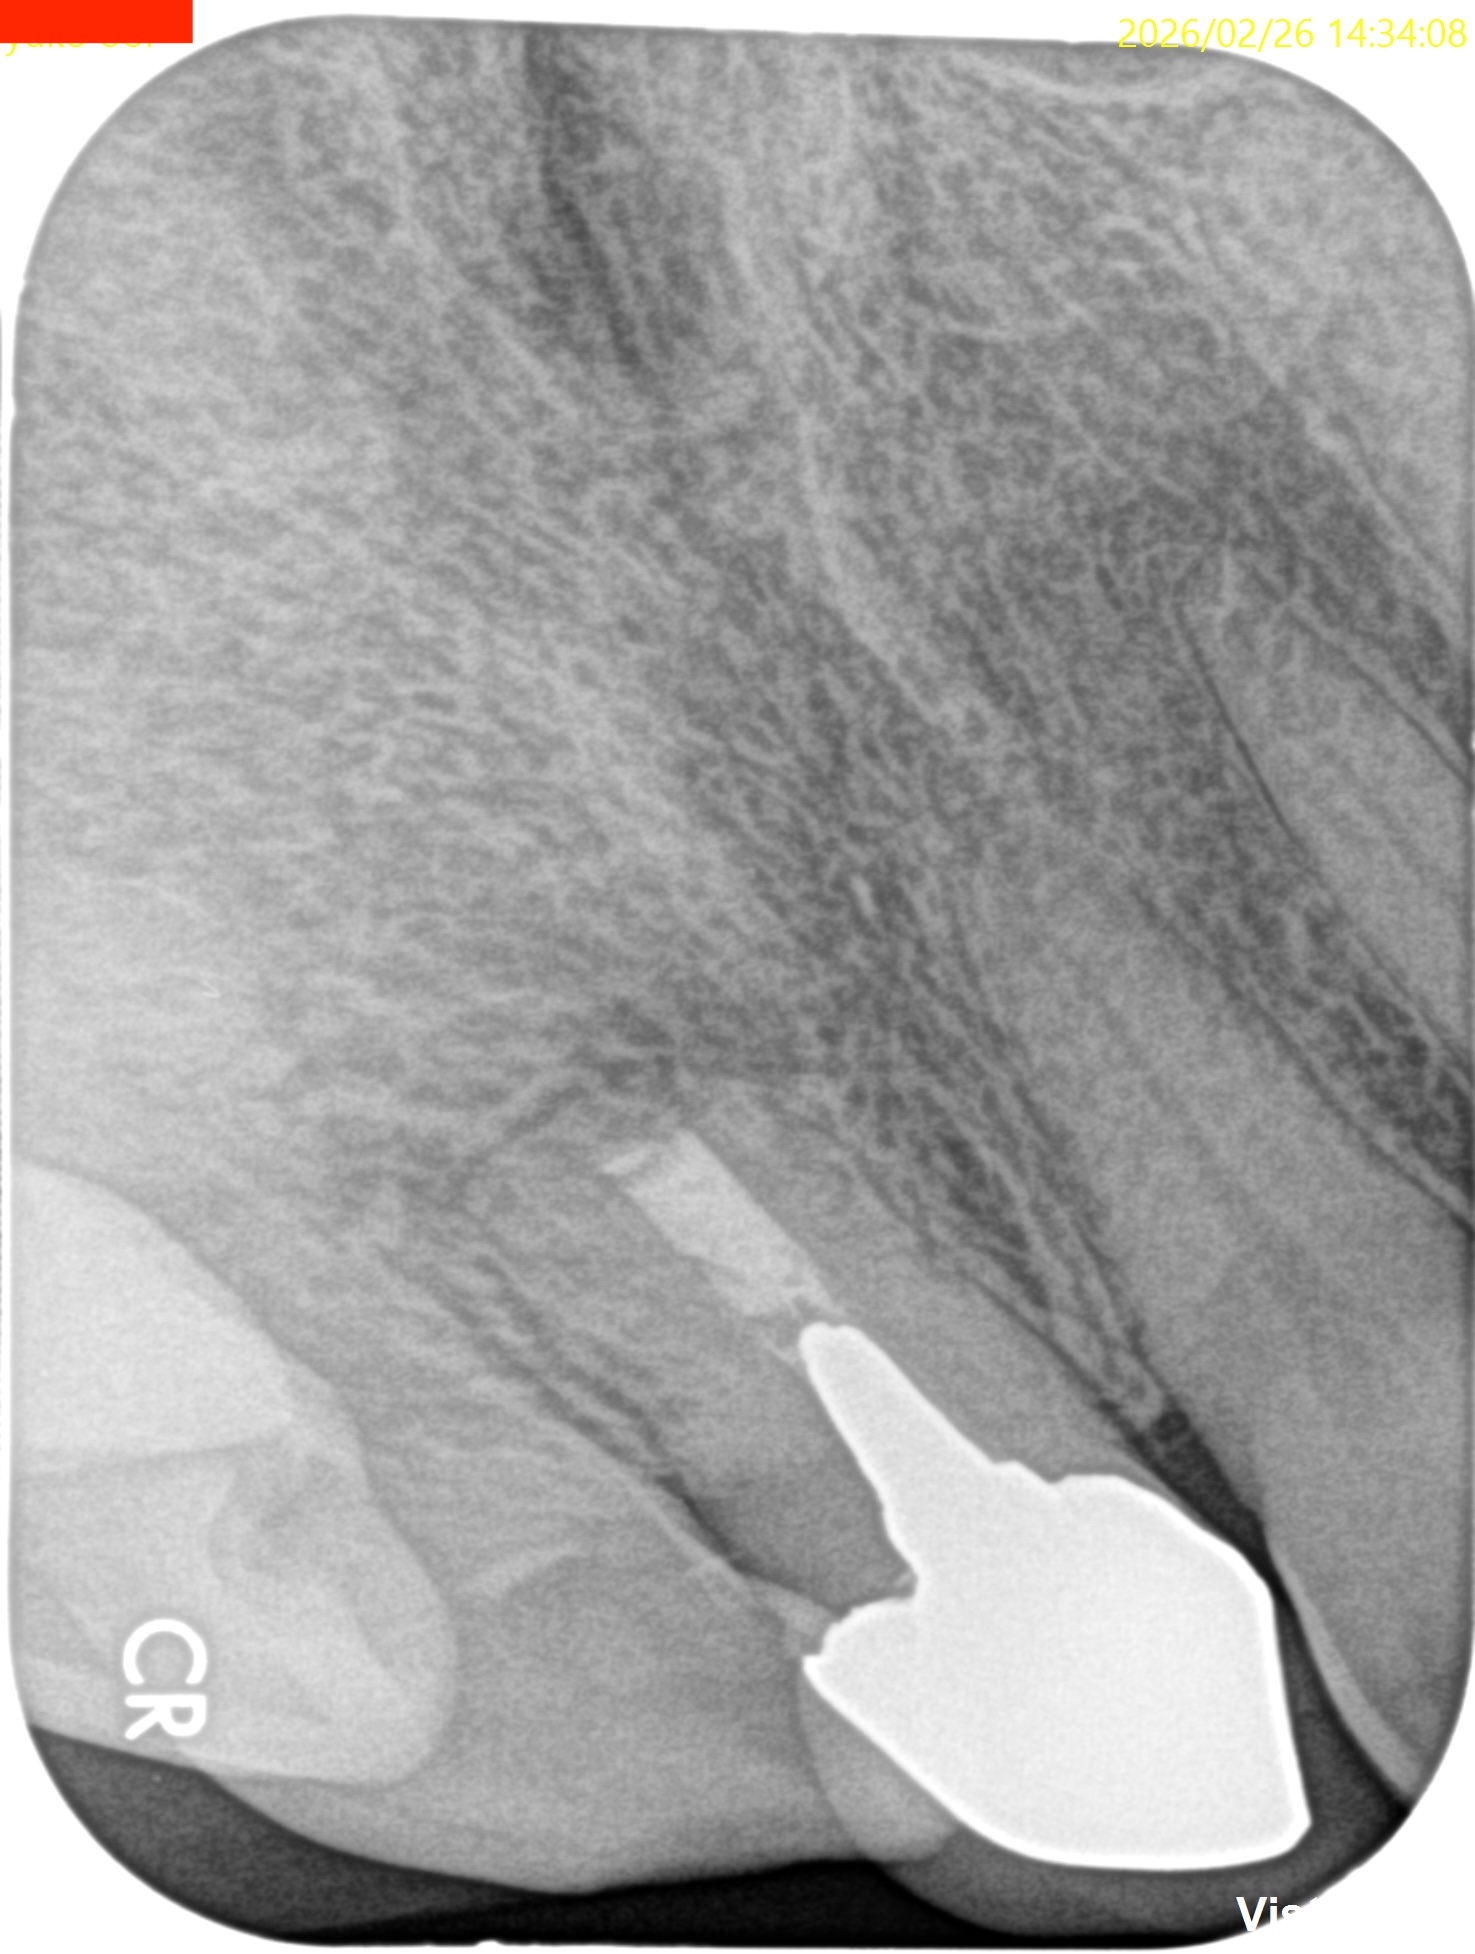

1年前と比較した。

1年前の#8の根尖は歯槽骨が全くなかったが、1年経過して90%がた回復した。

そして圧痛やSinus tractも消失している。

術前に反体側同名歯と比較して1mmしか根切していなかったのに、だ。